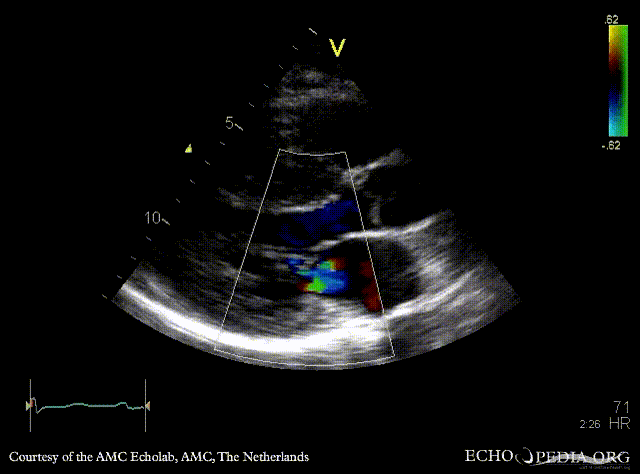

E00515.gif E00516.gif

A4CH: systolic obliteration of left ventricle, SAM of AMVL A4CH with Color Doppler: high velocity turbulent flow in LVOT and in the middle of left ventricle